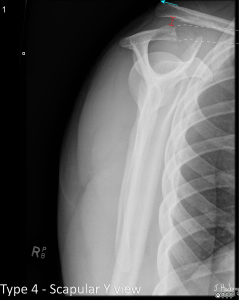

Grade IV

The clavicle is displaced posterior into the trapezius.